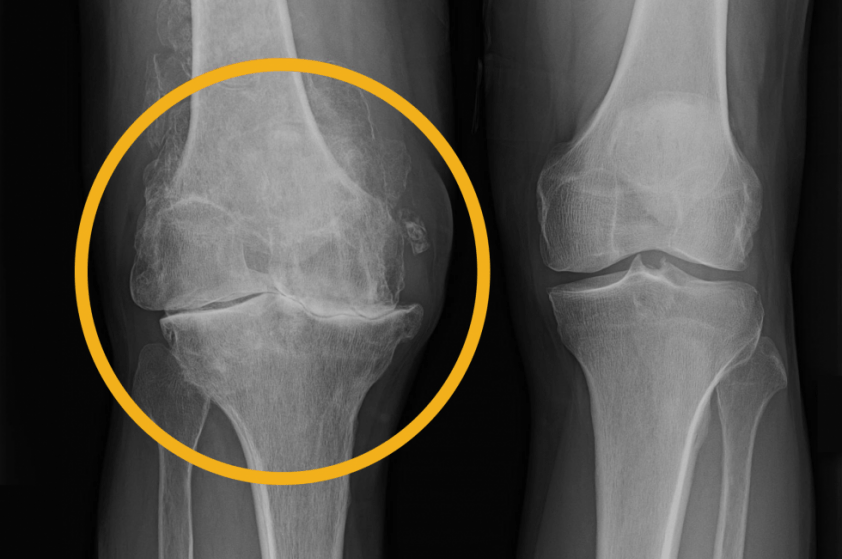

Aos 40, começou a sofrer de dores nas articulações. Aos 42 anos já havia recebido vários diagnósticos: osteocondrose, ciática e artrite.

Aos 68 anos, ela ficou incapacitada e foi diagnosticada com coxartrose do quadril.

As suas articulações estavam quase completamente desgastadas, e ela se movia com

muita dificuldade e apenas com a ajuda de uma bengala.